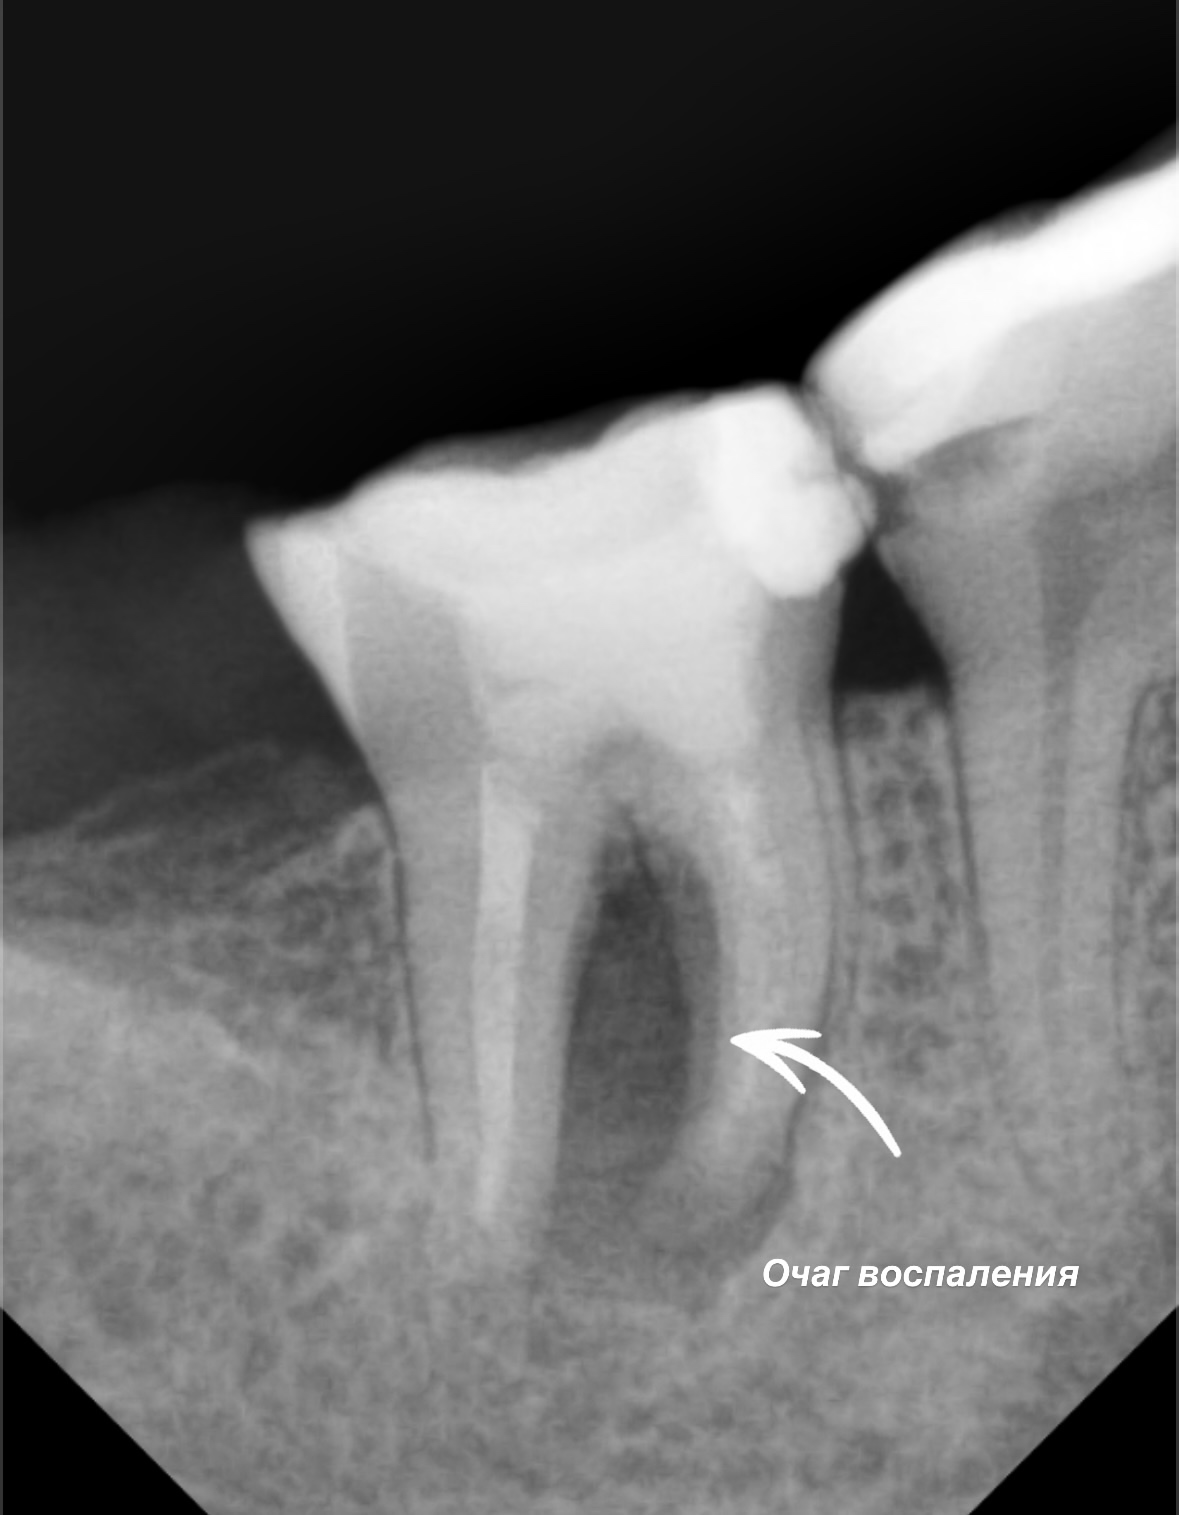

Эндодонтия